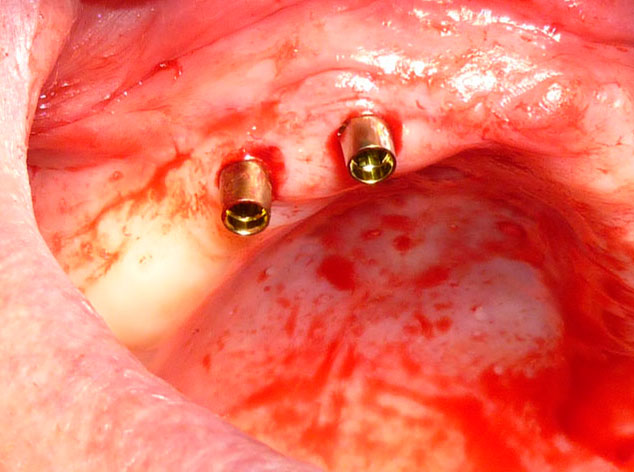

Es una cirugía básica y sencilla que generalmente se efectúa bajo anestesia local en motor consciente o con relajación en las Clínicas Santa Elena o Cemtro, si el paciente lo requiere.

Hoy se realiza de forma conservadora y poco invasiva mediante incisiones mínimas, por lo que es una cirugía poco agresiva que permite que el paciente pueda desarrollar su vida diaria con total normalidad.